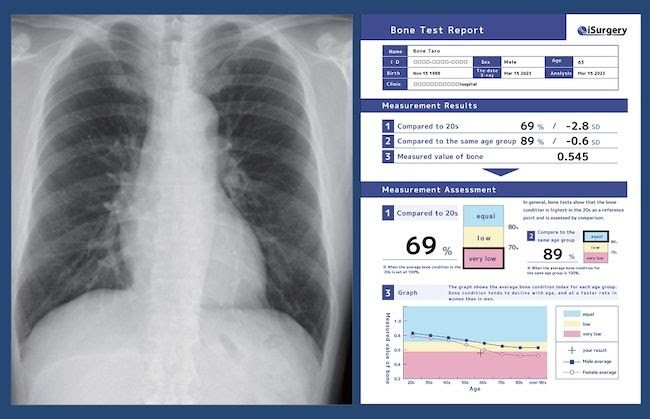

Fujitsu and iSurgery Launch Osteoporosis Detection Project with Jikei University

Fujitsu Limited and iSurgery Co., Ltd. announced that they will conduct a field trial as part of their “bone health promotion project” from October 2023 to March 2025 in collaboration with the Department of Orthopaedic Surgery at the Jikei University School of Medicine (1), to verify the practicality of bone assessments (2) conducted with chest radiographs and the effects of this approach in changing Fujitsu employees’ attitudes and habits around health. This marks the first time in Japan that ...